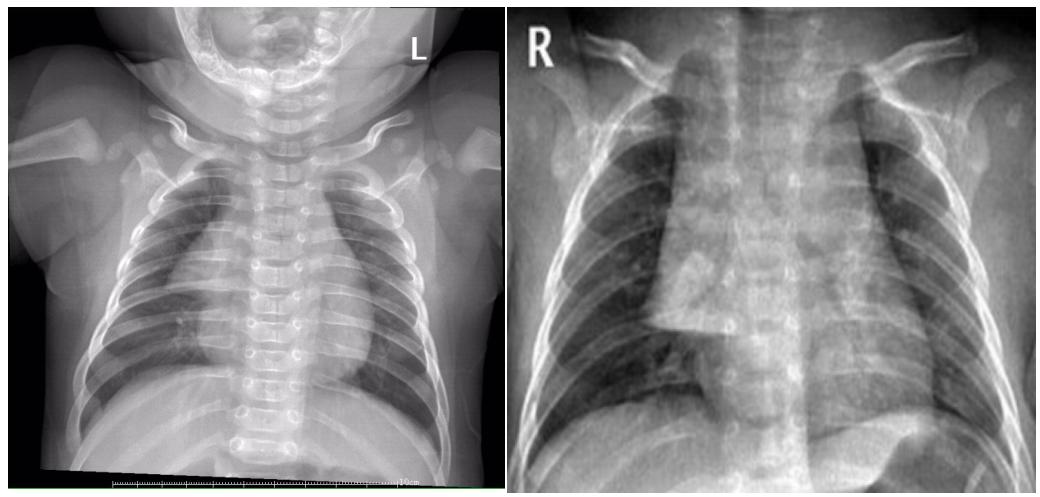

3、条形:双侧或单侧,致密均匀,内缘与纵膈相连,下缘位于水平叶裂位置,边缘均清晰锐利。如下图6所示。

图6示:条形胸腺影.

4、圆形:一侧或双侧,致密,圆形或半圆形,内缘与纵膈无明显分界,外缘弧线清晰锐利,亦有外缘模糊。如下图7所示。

图7示:圆形的胸腺影.